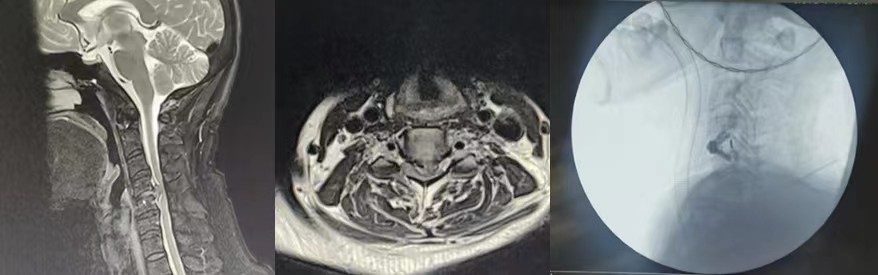

该患者为54岁维吾尔族男性,患者入院时行走已经较为困难,需家人搀扶,四肢无力、僵硬伴左上肢剧烈疼痛3月,因为手术风险极大,慕名新疆维吾尔自治区人民医院驻疆骨科专家前来就诊。杨宝辉医生接诊时发现该患者约80%的脊髓被突出的椎间盘及部分钙化物压扁,手术难度高,风险系数大,术中极有可能出现四肢瘫痪,缺血再灌注损伤等,这些无疑表明这是一个风险极高,难度极大的手术。但手术是患者唯一的选择,是挽救患者神经功能的唯一希望,在困难面前杨宝辉副主任医师决定迎难而上。

为了最大程度减少术中创伤,最终选择了颈前路单间隙减压植骨融合内固定的手术方式,并于2024年1月7日如期进行。术中杨医生发现椎体后缘几乎没有间隙,他机智地选择超声刮勺及神经勾巧妙配合,刮除钙化组织并缓慢勾出脱出的椎间盘组织,彻底显露硬膜及双侧钩椎关节,实现了彻底减压并置入融合器,最终神经诱发电位显示波幅上升,标志着手术的圆满成功。